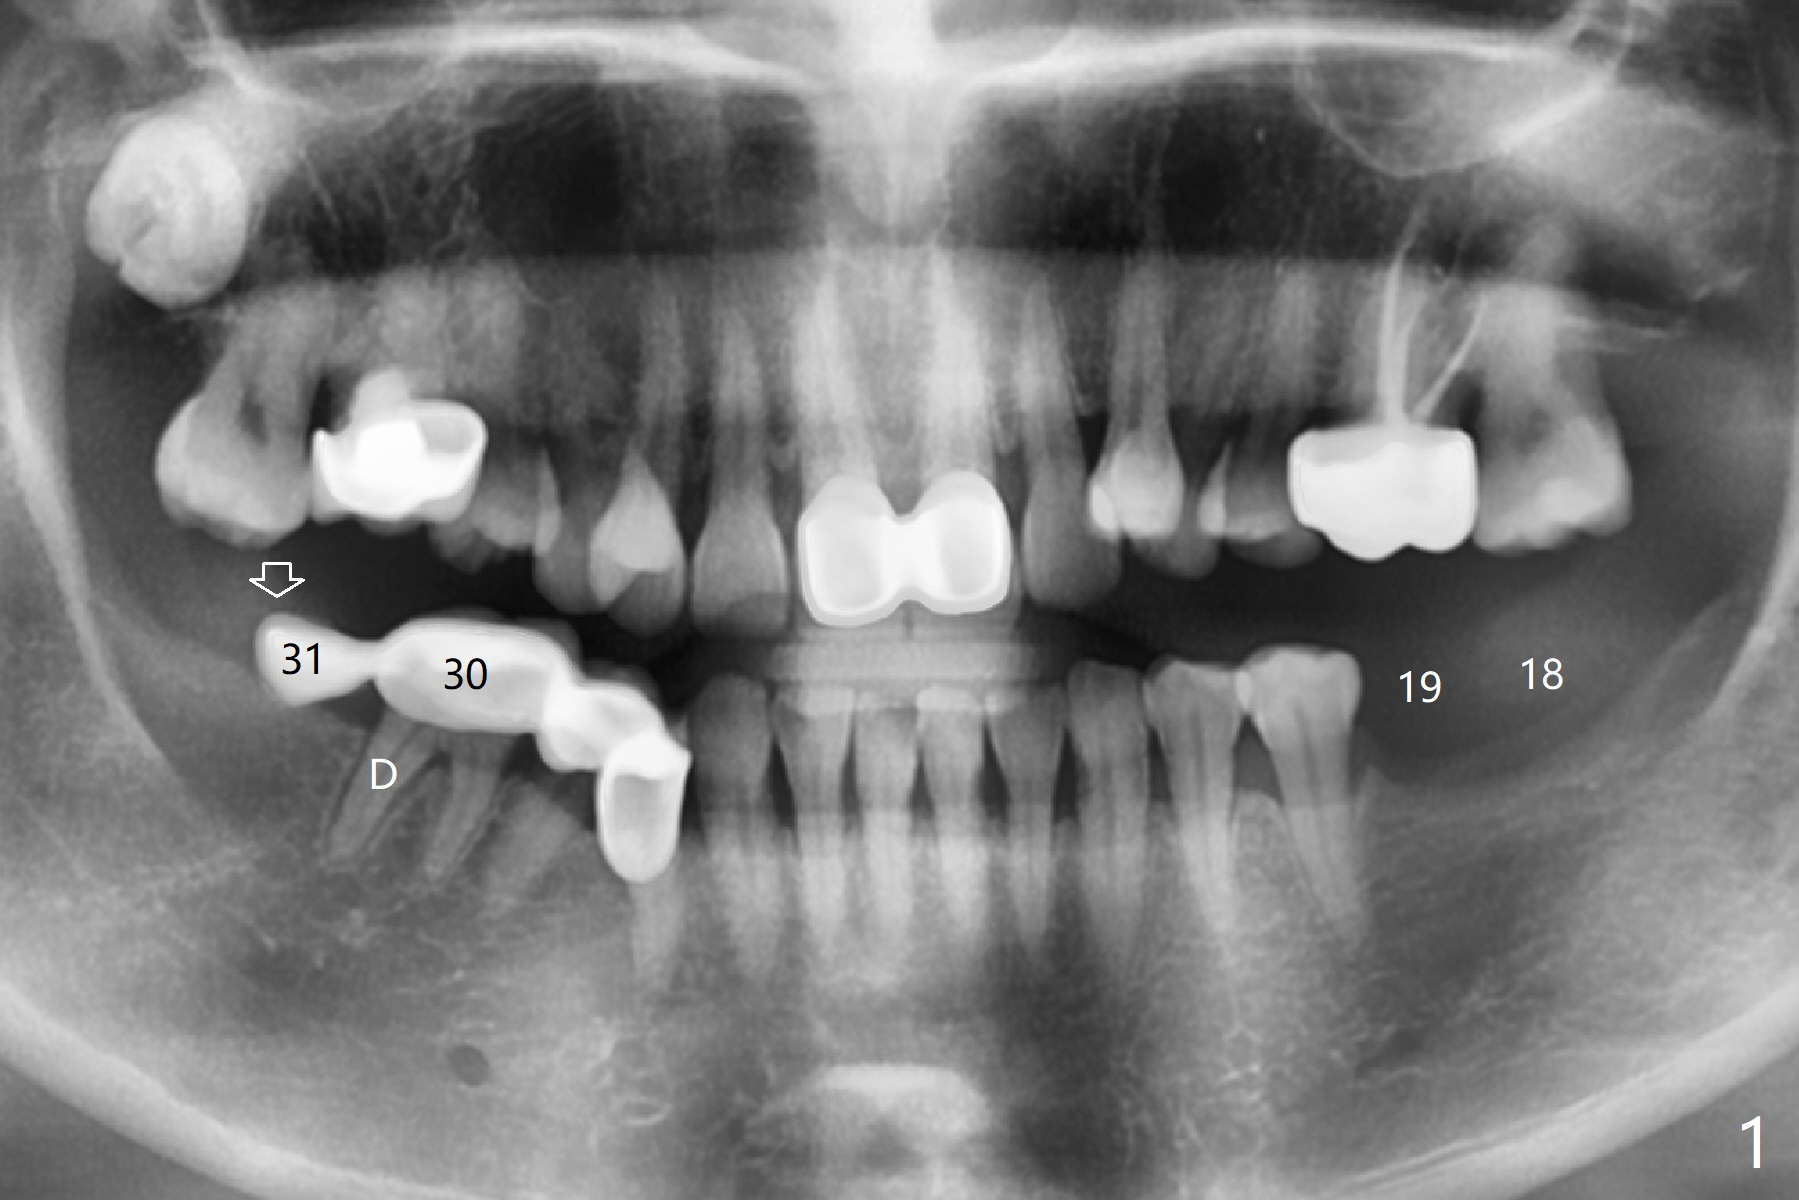

Edentulism